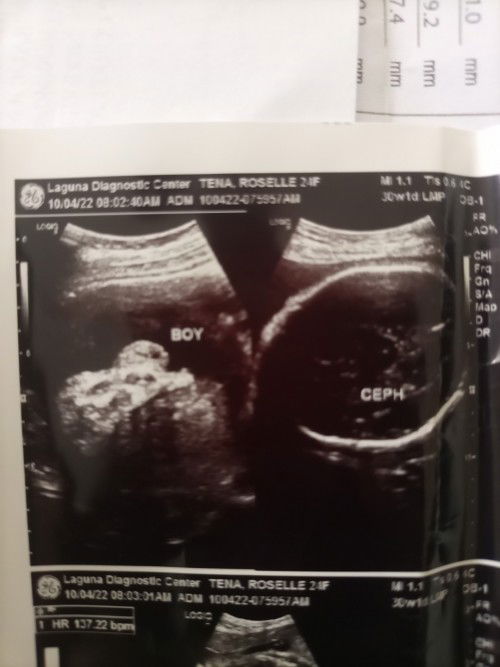

BOY SURE PO KAYA?

Sure po kaya na boy na? hehe Hindi po Kasi manlang tinuro sakin e. Thanks po❤️